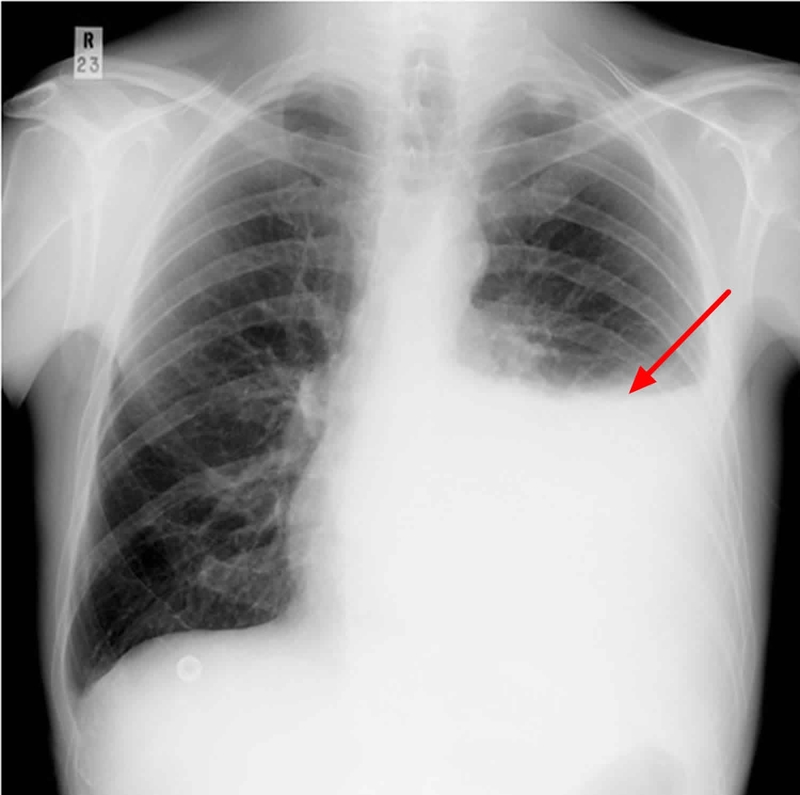

Trước khi giải đáp tràn dịch phổi có chữa được không, hãy cùng chúng tôi tìm hiểu về những dấu hiệu tràn dịch màng phổi mà bạn cần biết. Tùy thuộc vào nguyên nhân và mức độ tràn dịch màng phổi, bệnh nhân có thể gặp các triệu chứng lâm sàng rất khác nhau. Các triệu chứng thường gặp:

Tràn dịch màng phổi là triệu chứng hoặc biến chứng của nhiều bệnh phổi khác nhau, bao gồm viêm phổi, khối u ác tính và ung thư phổi. Các bệnh khác bao gồm áp xe dưới cơ hoành, áp xe gan, xơ gan cổ trướng, suy thận và suy tim.